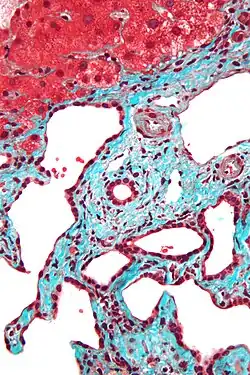

Micrograph of a bile duct hamartoma. Trichrome stain. Intermediate magnification -

Micrograph of a bile duct hamartoma. Trichrome stain, high magnification -

Low magnification micrograph of a bile duct hamartoma. Trichrome stain. -